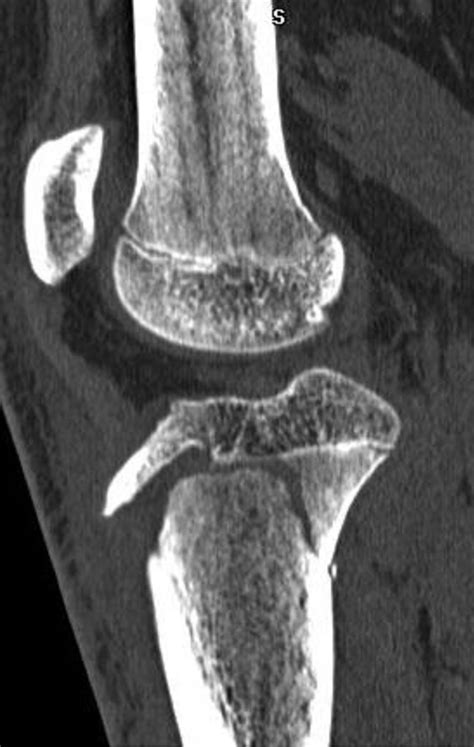

To confirm the diagnosis, physicians utilize a combination of physical examination and diagnostic imaging. Standard X-rays are typically sufficient to view the displacement, but in complex cases, an MRI or CT scan may be ordered to evaluate potential ligament damage or the involvement of the articular cartilage.